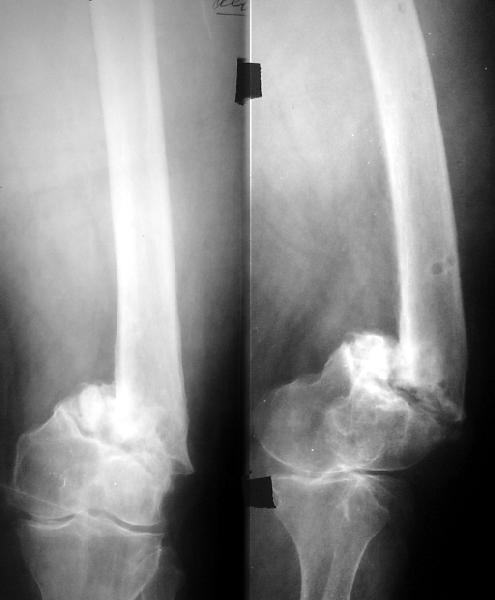

Вот давний пример похожего ложного сустава после неоднократных

остеосинтезов.